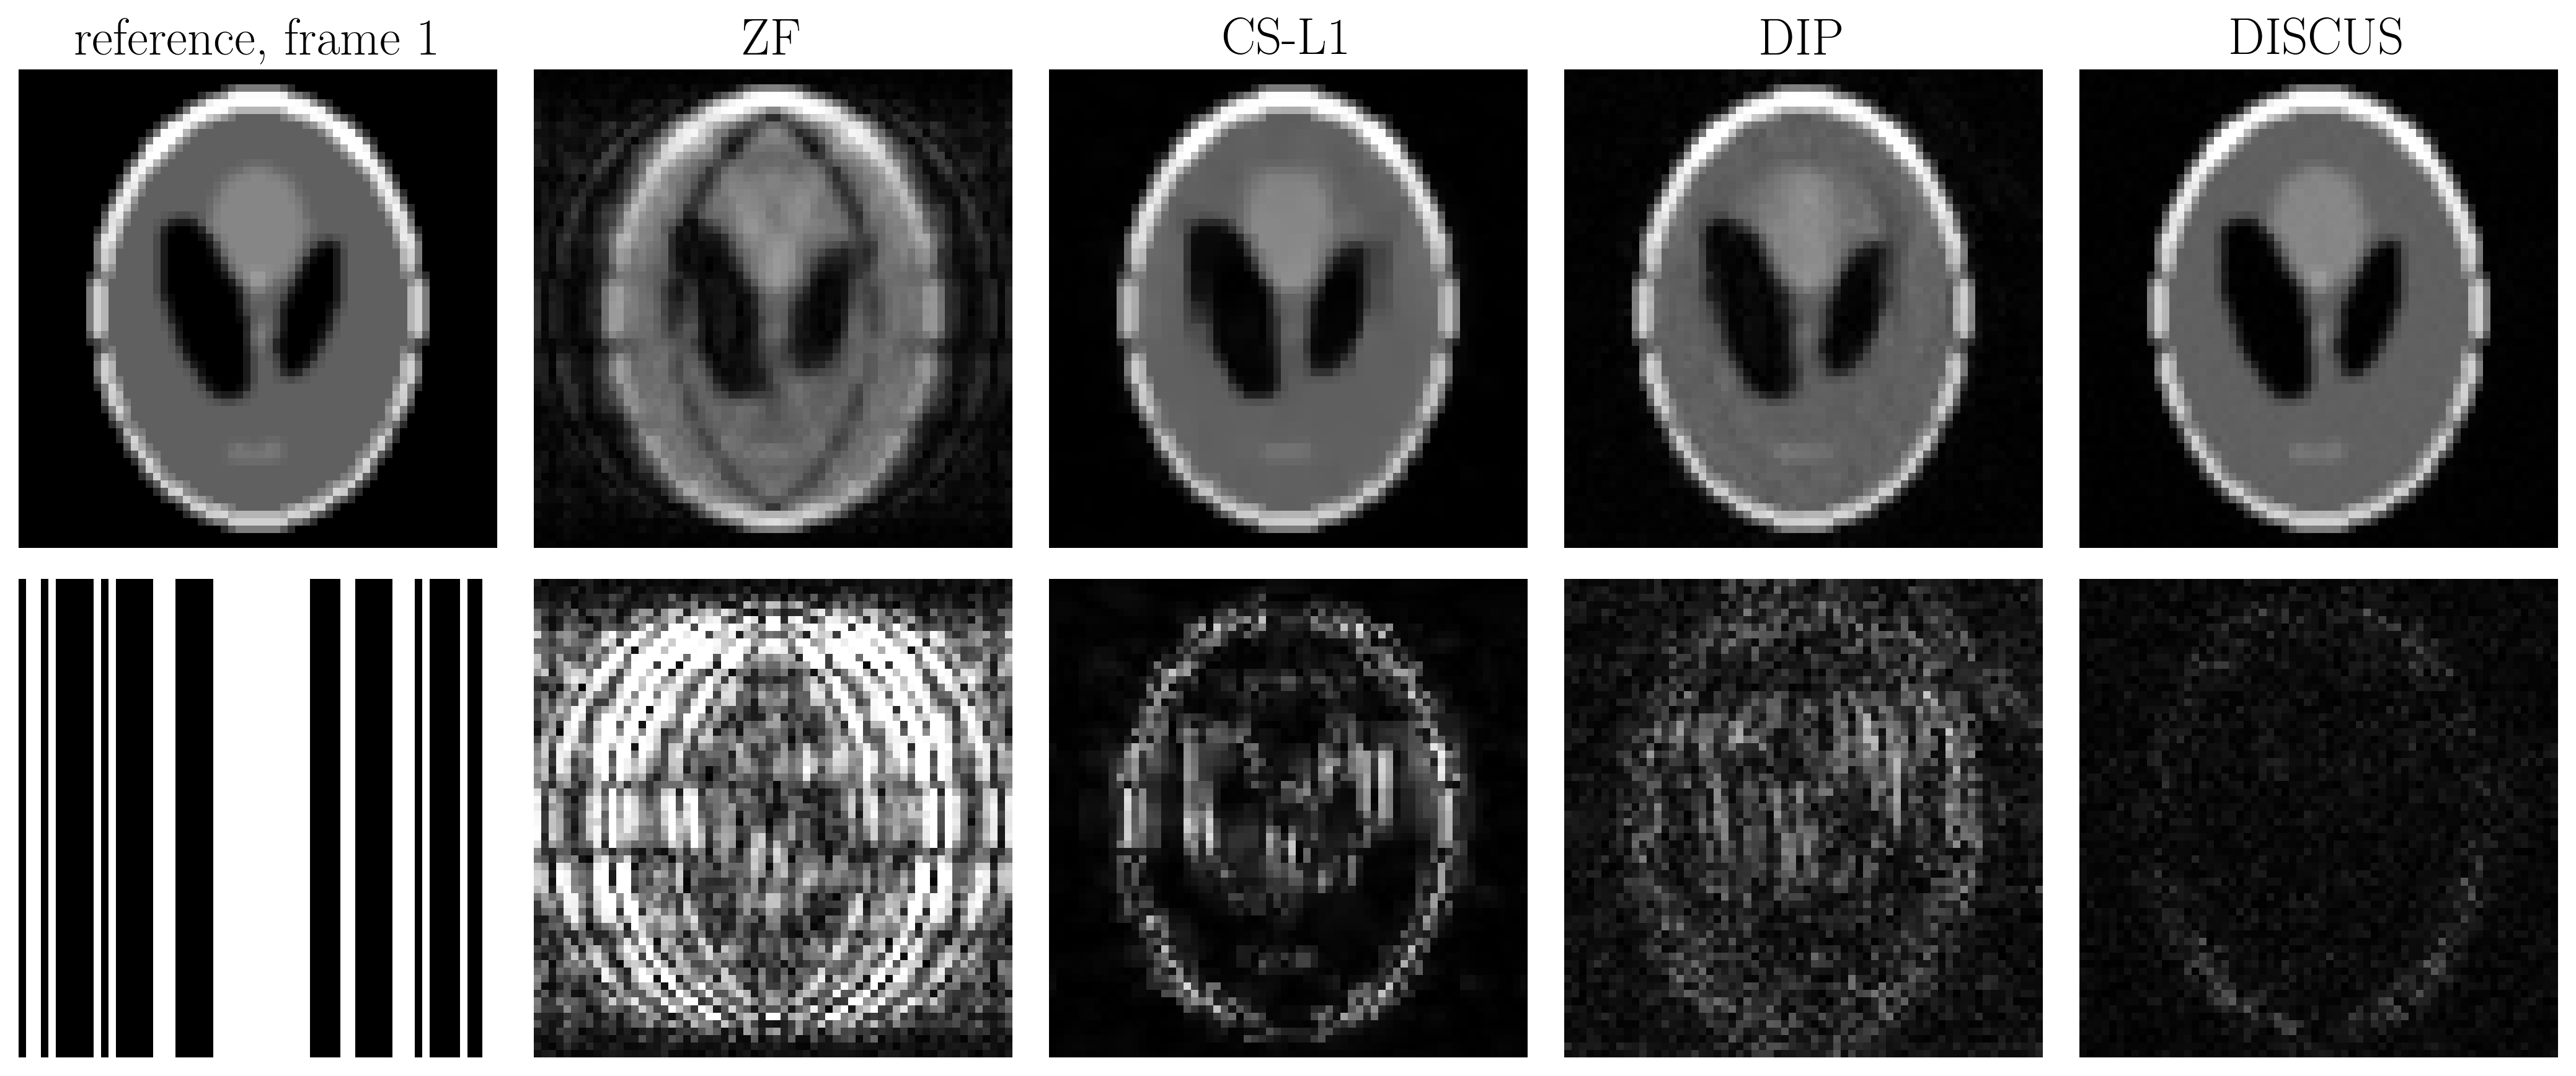

Table 1 shows the NMSE (in dB) and SSIM values for CS-L1, DIP, and the proposed DISCUS method for the three datasets. The values reported are an average over 32 frames for the phantom and 16 frames for HLA and SAX. In Figs. 1-3, the first column shows the reference frame (top) and the corresponding k-space sampling mask (bottom), and the next columns show reconstructed images (top) and corresponding error maps (bottom) of typical frames from these datasets.

Figure 1: Comparison of reconstructed images from a typical ($$$t=1$$$, in this case) phantom frame. Here, ZF stands for ''zero-filled''. The first column of the second row shows the k-space sampling mask. The rest of the second row shows error maps with five-fold amplification.

Our method outperforms CS-L1 and DIP by a considerable margin in terms of NSME (Table 1). DISCUS also outperforms other methods in terms of SSIM for HLA and SAX datasets. For the phantom dataset, CS-L1 shows higher SSIM, which can be attributed to the piece-wise constant nature of the Shepp-Logan phantom being well-suited for the sparsity based prior used in CS-L1. We also found that increasing the number of frames in series further improves NMSE and SSIM because more data facilitates manifold learning (data not shown). Figs. 1-3 indicate that DISCUS yields high quality reconstruction with visibly diminished artifacts. Interestingly, the number of non-zero entries, $$$m$$$, in each member of $$$\{\boldsymbol{z}_t\}_{t=1}^T$$$ for phantom, HLA, and SAX datasets was 1, 7 and 3, respectively. For phantom, $$$m=1$$$ correctly identifies the dimensionality of the underlying manifold (rotation) to be one. For HLA and SAX, one would expect a one-dimensional manifold originating from the respiratory motion. For HLA, $$$m=7$$$ can be attributed to sources of variation other than the respiratory motion, including timing of the RF pulses and beat-to-beat variations. Attempts to find a lower-dimensional manifold by forcing $$$m<7$$$ during the training resulted in worse NMSE and SSIM values (data not shown), which highlights the challenge of prescribing a manifold with predetermined dimensionality. In future, we will extend this work on multicoil MRI and a larger dataset.